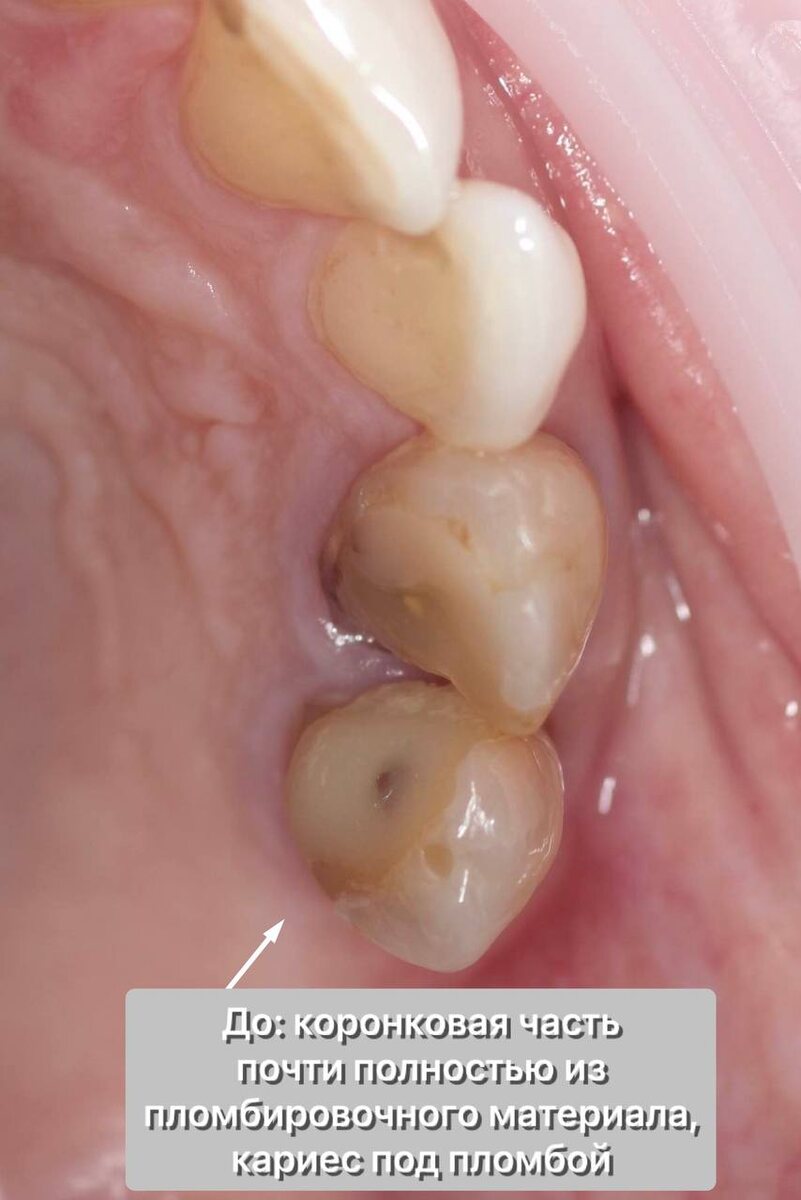

Всё как мы любим - зуб наполовину состоит из огромной дефектной пломбы, собственных стенок почти нет, кариес. Верхушка айсберга, самое интересное поджидало нас "на глубине, под толщей тёмной воды".

Но даже это мелочи - на Rg в канале различим металлический штифт, сам канал недопломбирован, визуализируется очаг деструкции на верхушке корня (периодонтит).